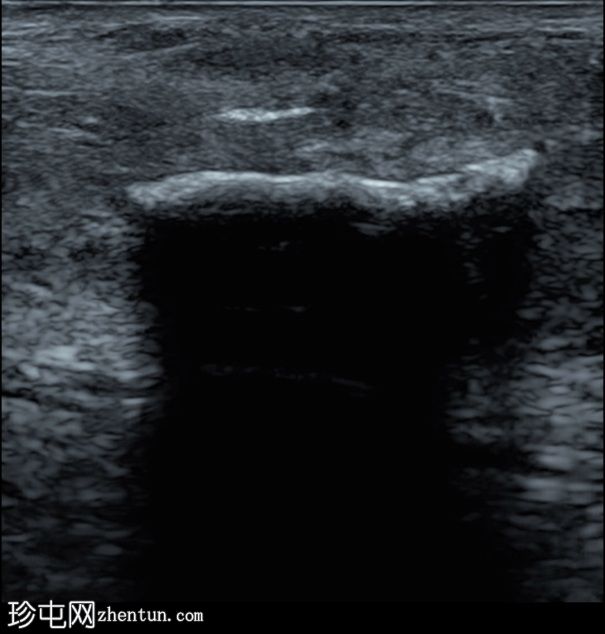

横切面

阴茎腹侧白膜内可见一纤维钙化斑块,位于阴茎海绵体和尿道海绵体之间。

阴茎海绵体内可见另一条线状纤维钙化斑块(横切面未显示)。

阴茎隔未受累。

白膜内的纤维钙化斑块提示佩罗尼氏病。

该条状回声伴后方声影,形似眉毛。